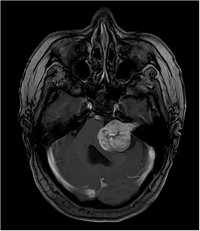

Akustikusneurinom T2 - axial

Akustikusneurinom T2 - axial - Vergrößerung